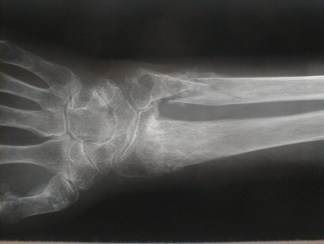

右前腕骨骨折

受傷時撮影1 受傷時撮影2

整復固定後再転位

再整復固定